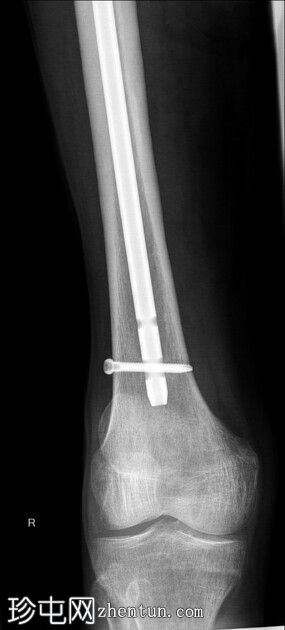

X光片

1.jpeg

正面

右侧髓内钉近端骨折(位于拉力螺钉孔位)。

空心髋螺钉组件完好。

股骨转子间骨折延伸至股骨近端转移灶,小转子粉碎。